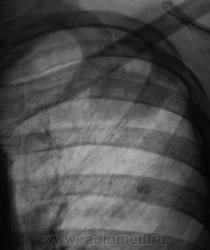

А, на верхушке, тихо "улыбалась" фокусная тень.

Жалоб нет. Ваше мнение уважаемые коллеги?

Прослеживается связь с корнем, плевра утолщена, рядом очаговая тень(отсев?), скоре всего туеркулез.

А, если туберкулёз, то, по всей видимости, инфильтративный?

Да, возможно даже каверна сформируется, фокус достаточно крупный, неоднородной структуры.

Наверно, тактически, правильно произвести томографию данной фокусной тени?

Тут,похоже еще и полости. Можно подумать и об " объемке". А что  в прошлом году? Или как всегда первичный?

учитывая отсутствие клиники, наличие неоднородной фокусной тени, отсев? на первый  план в диф. ряд можно выставить туберкулез, сделать Т-грамму левой верхушки, и пусть терапевты проведут минимальные обследования...

Слева в S2 похоже на туберкулому (очерченные контуры в отличии от инфильтрата).

Коллеги!!! Спокойный окружающий фон, отсутствие четкого контура, мелкая лучистость по периферии образования, лимфангит к корню, подходящая интенсивность. По-моему здесь классический периферический рак.

Во- первых:я бы сказал, что окружающий фон не совсем спокойный, т.к. за III ребром очаг.Во-вторых периферический рак лёгого (бронха), как правило растёт вдоль длинника бронха- мы этого в данном случае, не видим. В-третьих: при туберкулёзе, то же бывает "дорожка" к корню. Так, что говорить о классическом периферическом раке легкого не стоит.

Есть все основания для подозрений в сторону периферического рака...  Кроме того насторожила картина в нижней части правого корня - нет полоски Прозорова.